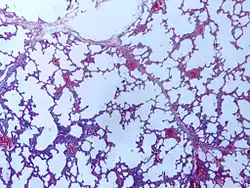

![]() |

Emphysema | Micrograph of empysema lung showing dialated, large alveoli separated by thin septa. Some septae are ruptured and appear to be floating in the alveloar spaces. Grossly emphysematous lung appears pale and voluminous. | Category: Histopathology of pulmonary emphysema | Emphysema |